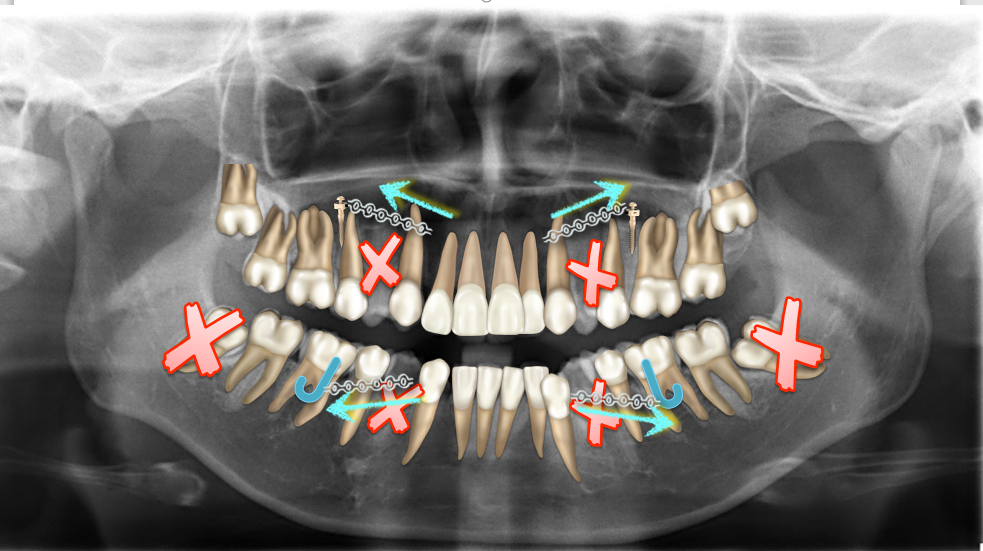

全景片

矫治计划:拔牙掩饰性治疗

1拔牙矫治,拔除14、24、34、44,上颌TPA+上颌高位支抗钉内收前牙及压低前牙,改善侧貌突度及露龈笑

拔除14、24、34、44,上颌TPA+上颌高位支抗钉

牙齿移动轨迹及生物力学

上后牙:高度保持不变/压入性移动,尽量避免伸长;▲垂直向控制中,应防止上后牙颊侧倾斜(TPA);▲腭尖高度控制也重要。

下后牙: 向前,整体移动利于咬合支点前移(Power arm);▲向前,倾斜移动易导致咬合平面后下旋转;▲后牙压低/全牙弓压低利于咬合平面逆时针旋转。

上前牙:向后,向上整体移动;

下前牙:向下,向后控制性倾斜移动。